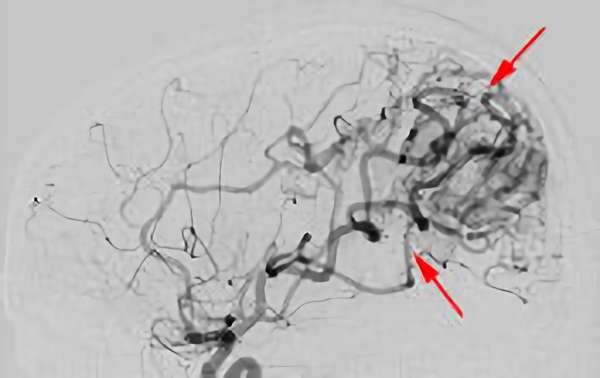

'26年3月

出血性脳動静脈奇形

10代

院内外来

No.1620 手術後